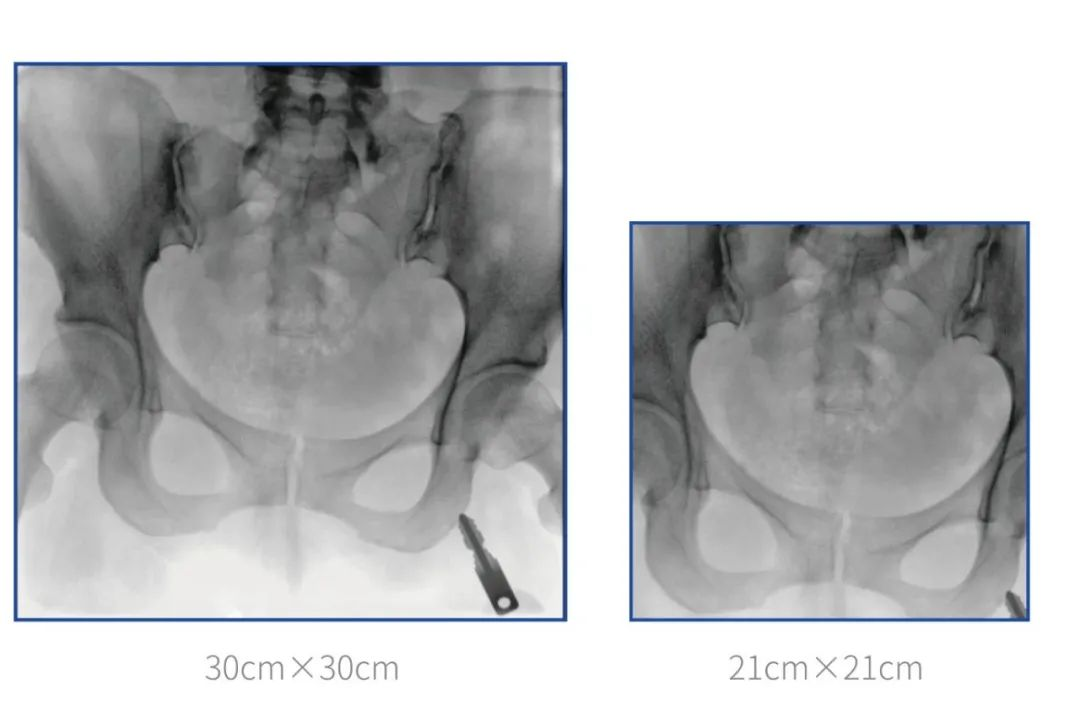

普愛醫(yī)療堅(jiān)持自主研發(fā)、持續(xù)創(chuàng)新,從臨床需求出發(fā),推出了大視野,能夠呈現(xiàn)更多圖像細(xì)節(jié)的大平板一體式C形臂。大平板一體式C形臂配置30cm×30cm平板探測器,對于諸如骨盆雙側(cè)骨折類型手術(shù)或骨盆后環(huán)內(nèi)固定術(shù)具有應(yīng)用優(yōu)勢,一次曝光可獲取全部骨折部位影像,可簡化曝光流程,提高手術(shù)效率!